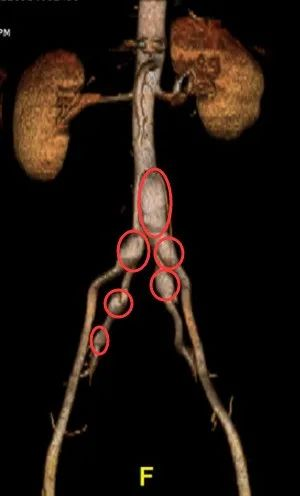

患者元先生,今年41歲,常年工作精神壓力很大,經常熬夜失眠,前不久因腿部出現大片淤青到醫院檢查,發現體內隱藏了多枚“不定時炸彈”——腹主動脈,髂總動脈級髂內動脈多髮夾層動脈瘤。主髂動脈夾層動脈瘤是一種危險性非常高的疾病,瘤體一旦破裂必將引起大量出血,常常趁人不備突然“爆炸”並迅速置人於死地,因此有體內不定時炸彈之稱。這意味著元先生的生命如同在走鋼索,有一點風吹草動就可能會引爆這一連串的“炸彈”,有性命之憂。 當地醫院沒有處理如此複雜多發的夾層動脈瘤的經驗,建議他儘快到大醫院進一步診斷治療。在朋友推薦下,他來到廣州醫科大學附屬第一醫院血管外科王海洋教授的門診求助。

“我們檢查發現,患者的動脈瘤樣擴張非常明顯,血管真腔被擠壓嚴重,直接影響血流供應,動脈瘤隨時有可能破裂。”王海洋教授立即安排元先生入院接受治療。

以往對於這種多發覆雜夾層動脈瘤的多采用手術開腹治療,但創傷巨大,風險極高,且盆腔血管重建遠期通暢率不高。“這位患者從上到下有大小不等的六個動脈瘤,如果開刀手術,切口會非常大,而且容易造成血管內膜撕脫,遠期生存質量會受到影響。”王海洋教授說,當前,腔內治療逐漸代替了傳統的開放手術,成為治療腹主動脈合併髂動脈夾層動脈瘤的首選術式。 但常規介入手術會採取“栓塞”的方式,用彈簧圈把有動脈瘤的兩側髂內動脈栓塞住,將瘤體完全封堵住,但這樣就等於兩條髂內動脈血管“報廢”,近期和遠期對盆底功能造成不良影響,比如出現腸道功能紊亂、性功能障礙等問題。

“我們考慮到患者還比較年輕,為了他日後的生活質量,我們還是希望能夠儘可能給他保住自體血管功能。”綜合各方面因素,經過反覆論證和精確評估後,王海洋教授決定“另闢蹊徑”,透過創新性地改裝現有覆膜支架,為元先生親手“縫製”了一套適合他血管特點的匹配度更高的內嵌式支架系統,既可以確保動脈瘤體的隔絕,又同時做到髂內及髂外動脈的重建,以保留其自身血管原有功能。

手術過程中,先透過股動脈穿刺進入腹主動脈,保證支架和動脈壁良好貼附,重建好這條“主幹道”之後,又透過上肢動脈血管將量身定製的內嵌式支架欲埋導絲,精確定位,完美實現髂內動脈的重建,保證盆腔的血液供應。 近三個小時的精細化操作,王海洋教授順利為元先生摘掉了那六枚隨時可能爆炸的“體內炸彈”,並且保留了髂內動脈血供,使得患者未來的生活質量有了保證。術後造影顯示,血液在其腹主動脈及兩側的髂內,髂外動脈“暢通無阻”。